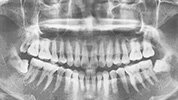

当日は、簡単なレントゲン、口腔内写真を撮り、おおよその状態を把握いたします。

現在のお口の状態・かみ合わせに関して多くの項目の精密検査を行います。

初期治療が必要だった患者さんは、初期治療終了後、再治療にならないための再度精密検査いたします。現在のお口の状態・かみ合わせに関して多くの項目の精密検査を行います。

必要に応じてレントゲン、口腔内写真などの検査を行います(メンテナンス費用に含まれます)